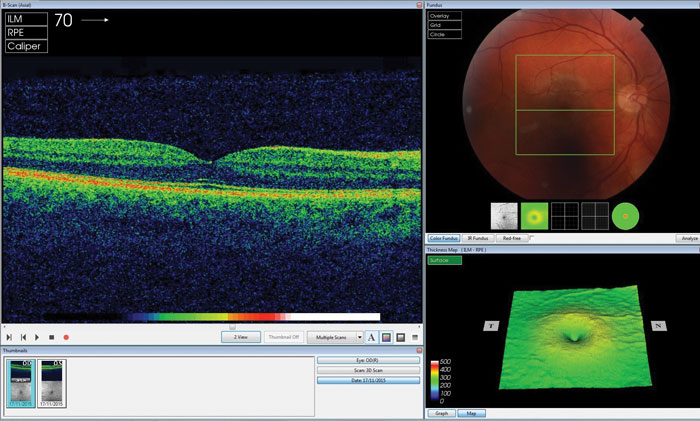

Figure 1: Analysing an OCT scan. Source: Courtesy of DeepMind Technologies.

The deep learning framework features two separate neural networks: a segmentation network that creates a detailed device-independent tissue segmentation map and a classification network that analyses this map and provides diagnoses and referral suggestions (Figures 1-3). The training set for the classification network was 14,884 OCT scan volumes of 7621 patients. The system also explains its decisions: first, with an interpretable segmentation or visual ‘map’ of pathology features identified on the OCT images and second, generating predicted probabilities for the level of confidence it has in its diagnoses and referral suggestions.